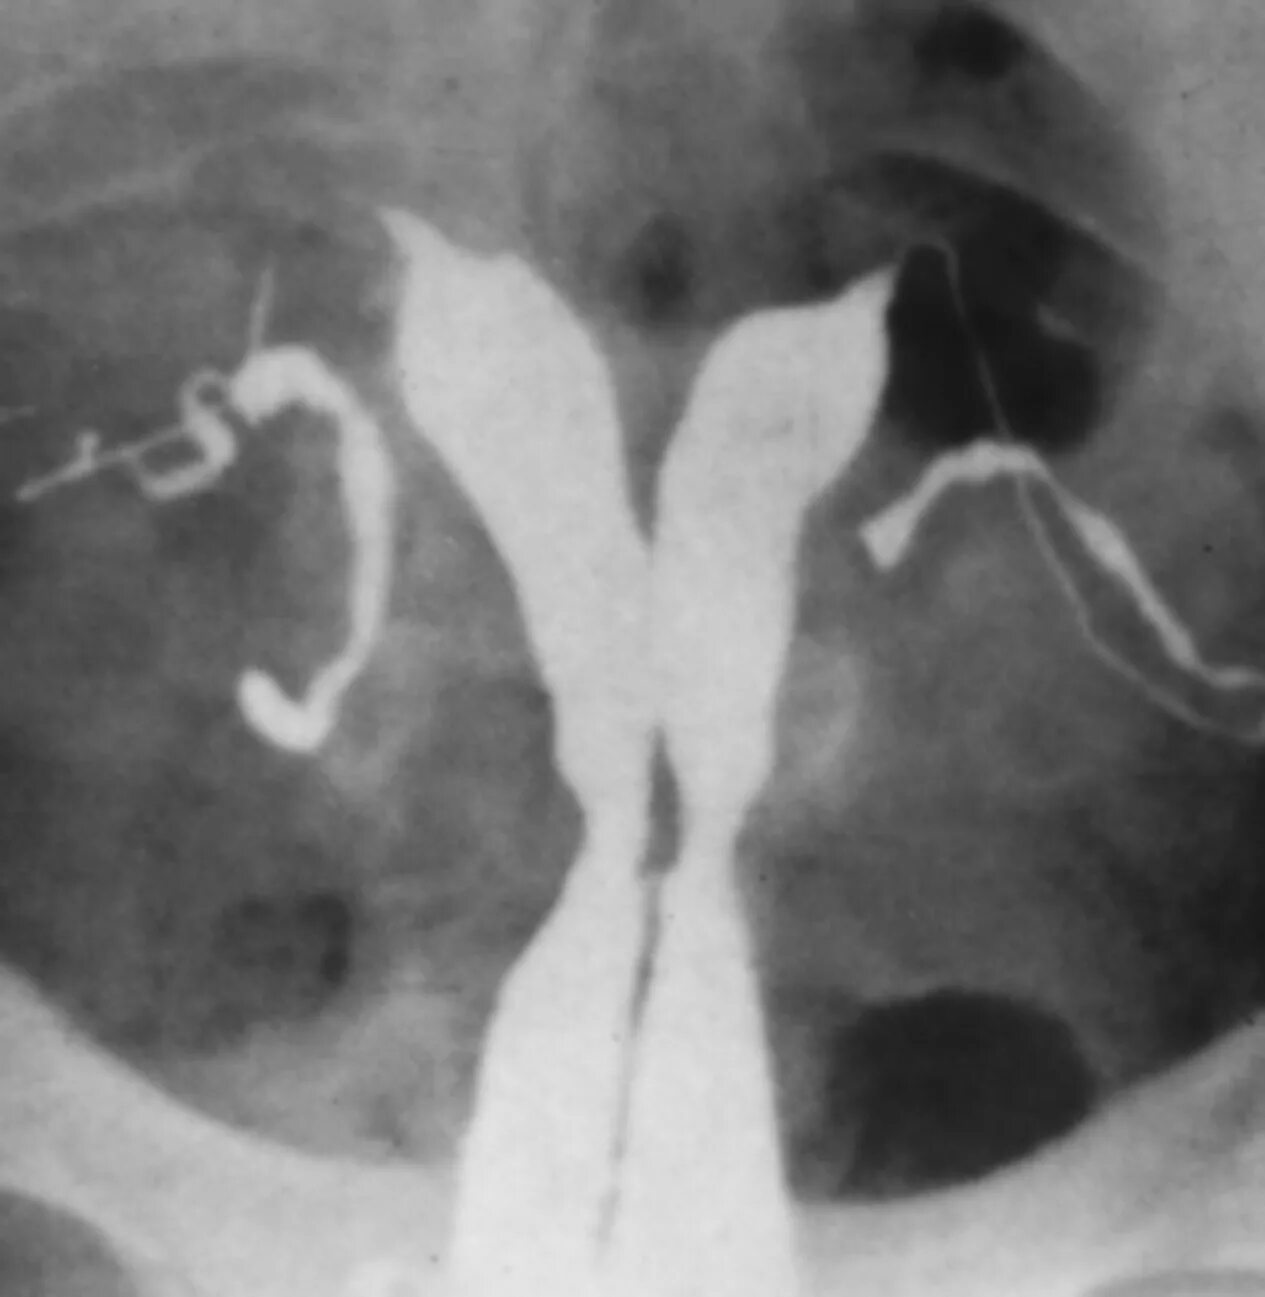

Аномалия полов орган